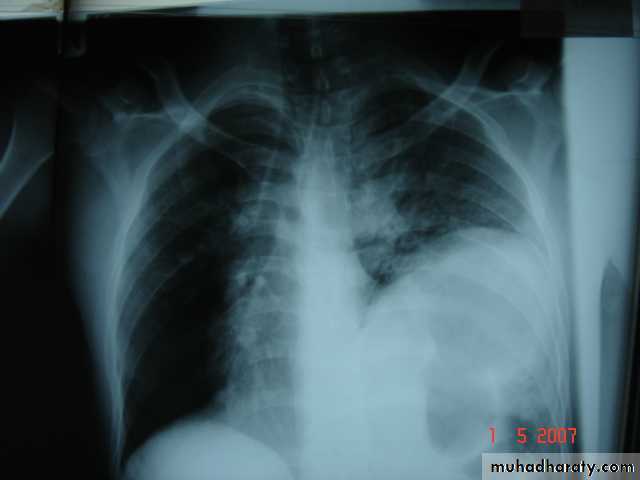

• Radiological Findings

• 1-Smooth homogenous opacity (Intact H.C).• 2-Partial rupture (per vesicular pneumocyst).

• 3-Complete rupture (Water –lilly sign) .

• 4-Formation of lung abscess(Air –fluid level) .

• 5-Completely coughed out cyst(empty cavity )

• 6-Rupture into the pleura (hydropneumothorax)

• A-Asymptomatic• Any smooth homogenous opacity of uniform density with clear cut border and little or no reaction around it on a chest X-Ray is a hydatid cyst unless proved the other wise .